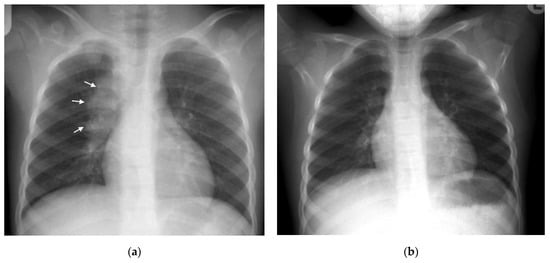

Figure 2. (a,b): Left hilar lymphadenopathy on the PA and lateral chest radiographs. (a) PA erect chest radiograph in this child with later confirmed pulmonary TB demonstrates a multilobulated lymph node mass projecting beyond the cardiac margin on the left (white arrows) consistent with left hilar lymphadenopathy. There is also loss of the left cardiac margin consistent with lingula air-space disease/atelectasis as a consequence of left main bronchus compression (black arrow). (b) Lateral chest radiograph confirms the presence of hilar lymphadenopathy by demonstrating an oval mass consistent with the ‘doughnut sign’ (curved white arrows), representing lymphadenopathy inferiorly and likely the normal vessels (aortic arch and left main pulmonary artery) superiorly.

Right hilar adenopathy (a lobulated hilar opacity on chest radiograph) obscuring the hilar point, Figure 1, is more commonly observed than left, with left hilar nodes only evident when extending beyond the left cardiac border [27]. Paratracheal adenopathy may be difficult to distinguish from other mediastinal tissues, such as the thymus, but will extend beyond the normal mediastinal contours, and may result in airway compression and deviation [27]. Left paratracheal lymphadenopathy is rarely observed in isolation, most commonly co-existing alongside other regions of mediastinal lymphadenopathy [27]. Sub- or retro-carinal lymphadenopathy is typically seen on the lateral projection as lobulated densities inferior and posterior to the bronchus intermedius, which, in combination with the more superior aortic arch and pulmonary arteries result in the well described “doughnut sign” (Figure 2).

CT can identify lymphadenopathy in a significant proportion of children with PTB and normal chest radiographs [13]. On post-contrast CT, TB lymphadenopathy typically appears as having low attenuation centrally with peripheral rim enhancement [2] (Figure 3). The central region of low attenuation represents caseous necrotic tissue seen in tuberculous lymphadenopathy, enabling this to be distinguished from non-TB adenopathy. Alternatively, TB nodes may form a matted conglomerate with ‘ghost-like’ rim enhancement [16]. Moderately enlarged lymph nodes may occur in bacterial pneumonia, but rarely having areas of necrosis or calcification [15].